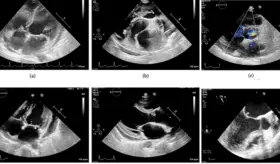

El cuadro se caracterizó por neumonía necrotizante, aleteo auricular con respuesta ventricular rápida, insuficiencia cardíaca biventricular y formación de trombos intracardíacos bilaterales.